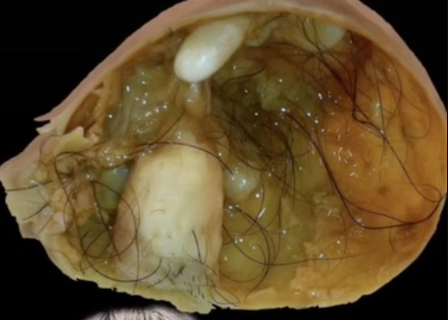

Yavuze ko ubwo abaganga bagezaga icyuma hafi y’imyanya y’ibanga babonye mu nda ye harimo ibintu bidasanzwe aho babonye muri nyababyeyi ye harimo amenyo abiri n’imisatsi bigenda bikura kandi ko abimaranye imyaka ibiri bikura.